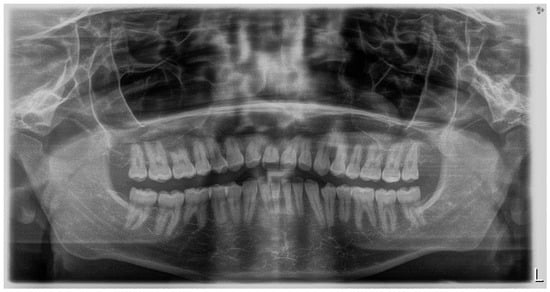

Panoramic radiography, performed in 28 November 2018 (Densply Sirona, Charlotte, NC, USA, Orthophos SL 2D), revealed a full dentition and shortened tooth root length: 24, 25, 31, 32, 33, 34, 35, 41, 42, 43, 44, 45. The X-ray is presented in Figure 3.

Figure 3. Pre-treatment panoramic radiograph.